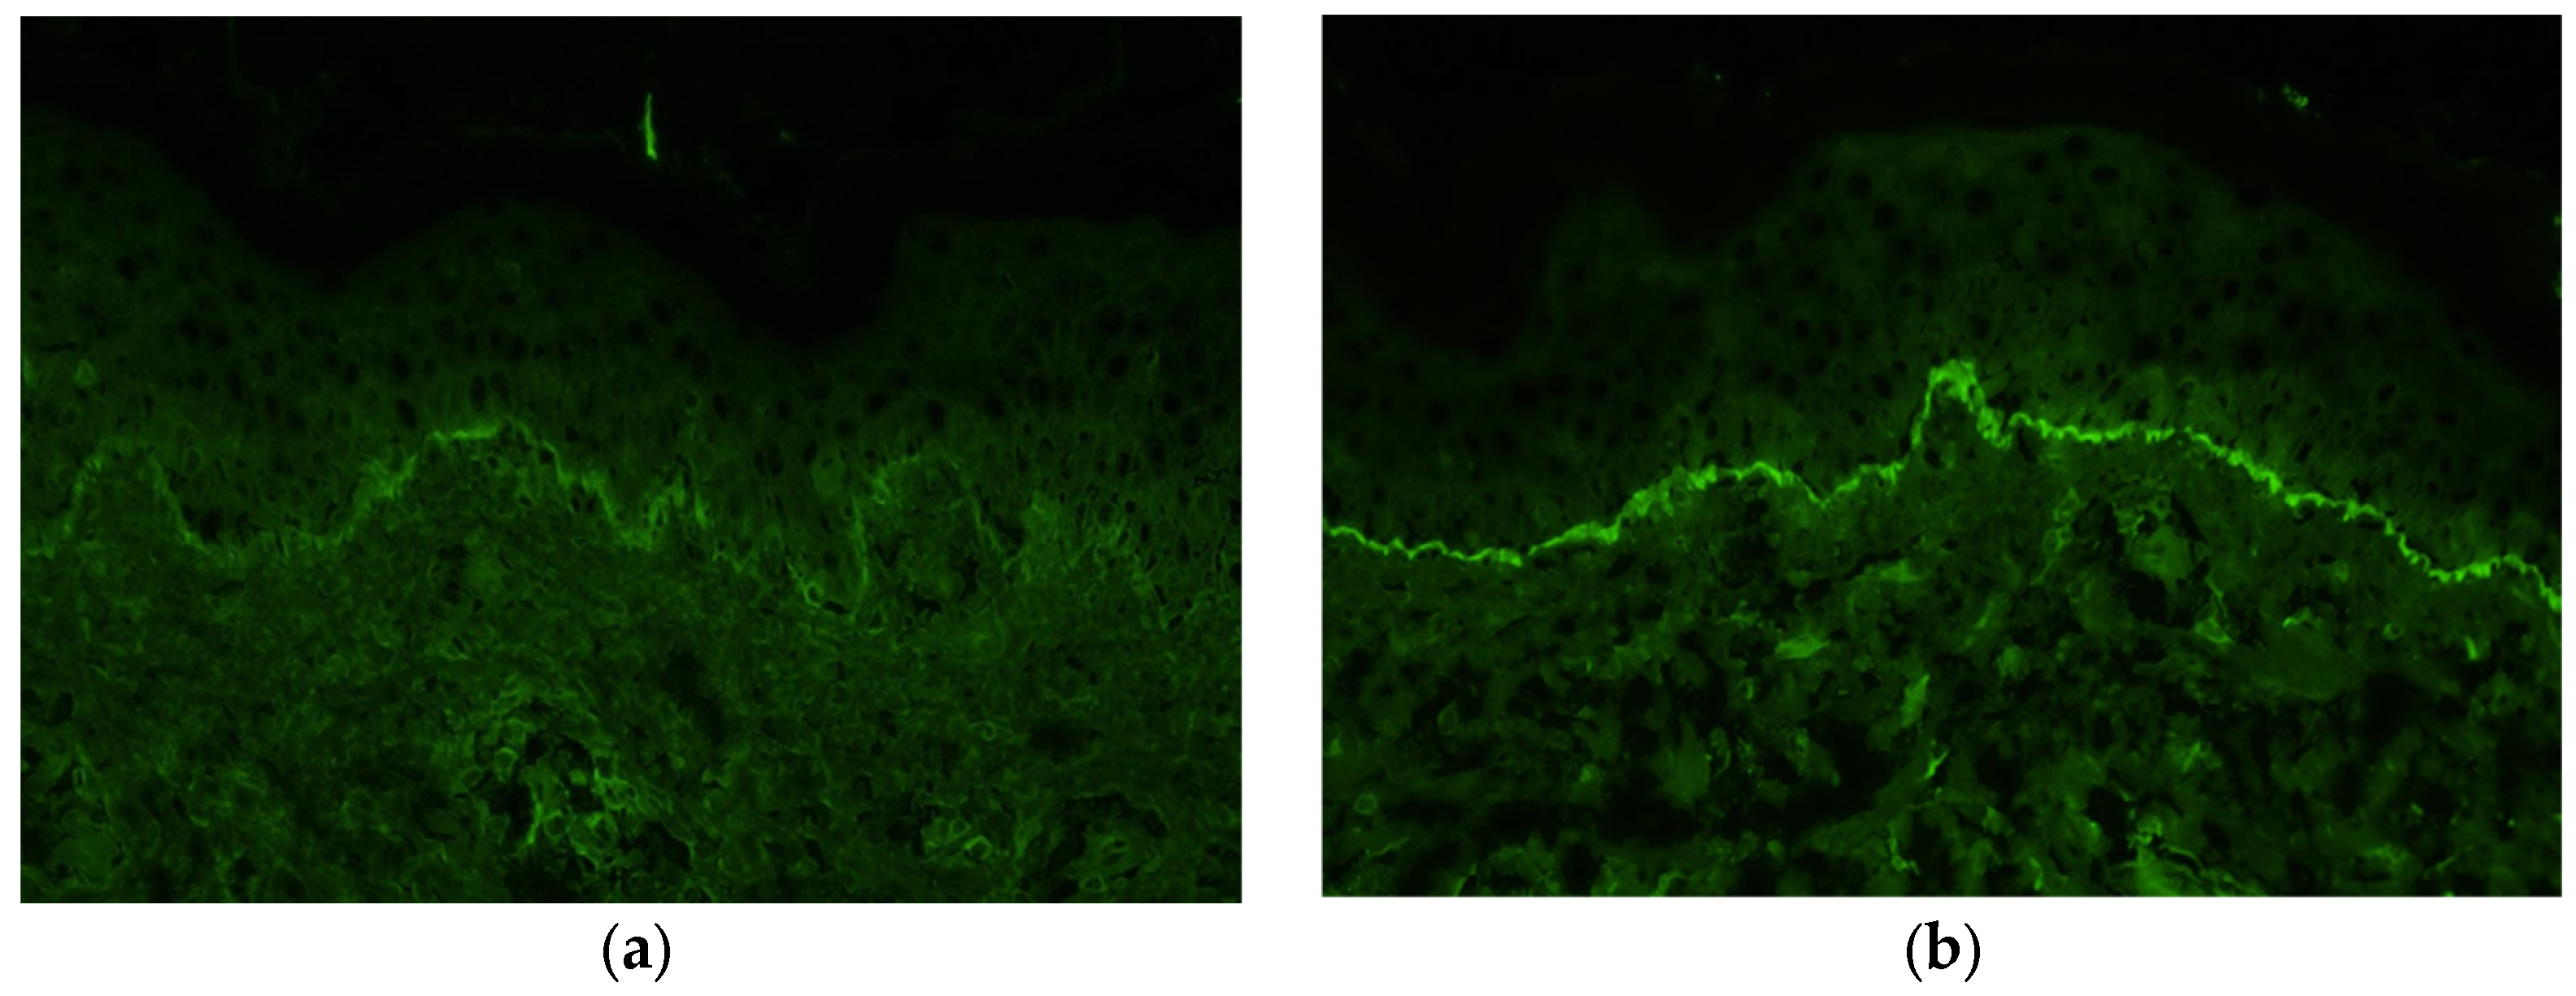

2. Case Presentation

3. Discussion